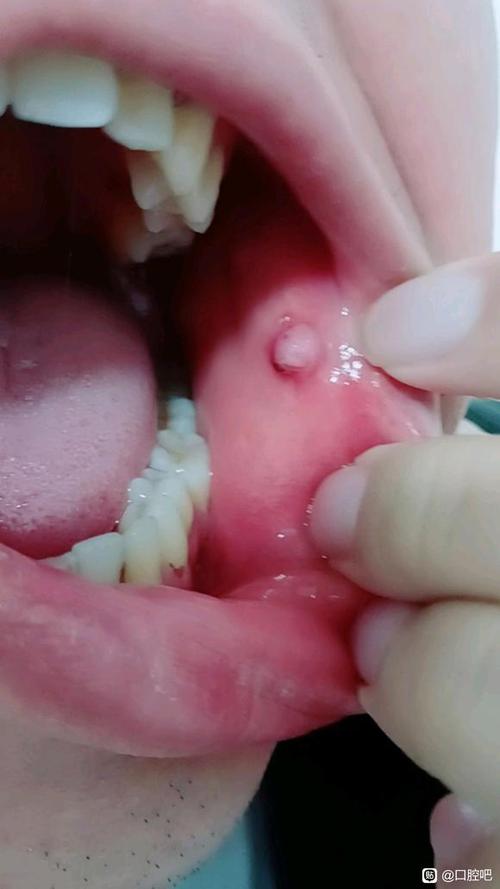

粘液腺囊肿

- 特点:通常是由于小唾液腺的导管被堵塞,导致唾液潴留而形成的半透明、柔软的小水泡或肉疙瘩,表面光滑,呈淡蓝色或正常粘膜颜色,一般不痛,但如果受到刺激或破裂,会引起肿痛和不适。

- 位置:常见于下唇内侧、舌尖、颊粘膜等部位。